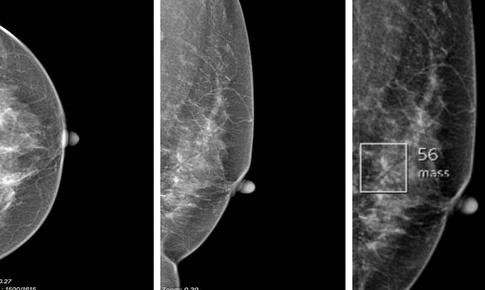

Trí tuệ nhân tạo (AI) giúp phát hiện chính xác ung thư vú

Sức khỏe sinh sản - 02/09/2025 08:35SKĐS - Trí tuệ nhân tạo (AI) đang đóng vai trò ngày càng quan trọng trong việc phát hiện ung thư vú, đặc biệt là thông qua phân tích hình ảnh y tế. Trong tương lai AI sẽ là một công cụ hỗ trợ giúp nâng cao độ chính xác và tốc độ chẩn đoán bệnh.

Hình ảnh - chìa khóa trong chẩn đoán và điều trị ung thư vú

Y tế - 13/08/2025 08:00Hình ảnh học đang trở thành "chìa khóa" trong phát hiện sớm và điều trị ung thư vú, đặc biệt khi kết hợp trí tuệ nhân tạo và các kỹ thuật can thiệp ít xâm lấn.